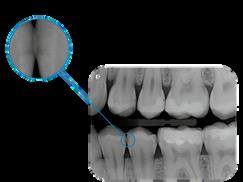

1 Orthogonal panoramic X-ray: minimises the overlapping of adjacent teeth and provides better periodontal analysis

2 Fast panoramic X-ray: low dose and reduced scan time, perfect for primary investigations, follow-ups or uncooperative patients

3 Child panoramic X-ray: limited exposure and optimised parameters for fast paediatric examinations.

4. Complete dentition divided into quadrants: localised investigations with selectable segmentation to limit the irradiated dose.

5. Bitewing projections limited to crowns: high resolution and low dose, a comfortable alternative to intraoral imaging, appreciated by patients with a strong gag reflex.

Innovative DCIII technology, which improves depth of field and increases contrast - and therefore real resolution power - lets users obtain SuperHD panoramic images from extremely extensive datasets to provide an 11-layer MultiPAN. Highly useful in the case of complex morphologies